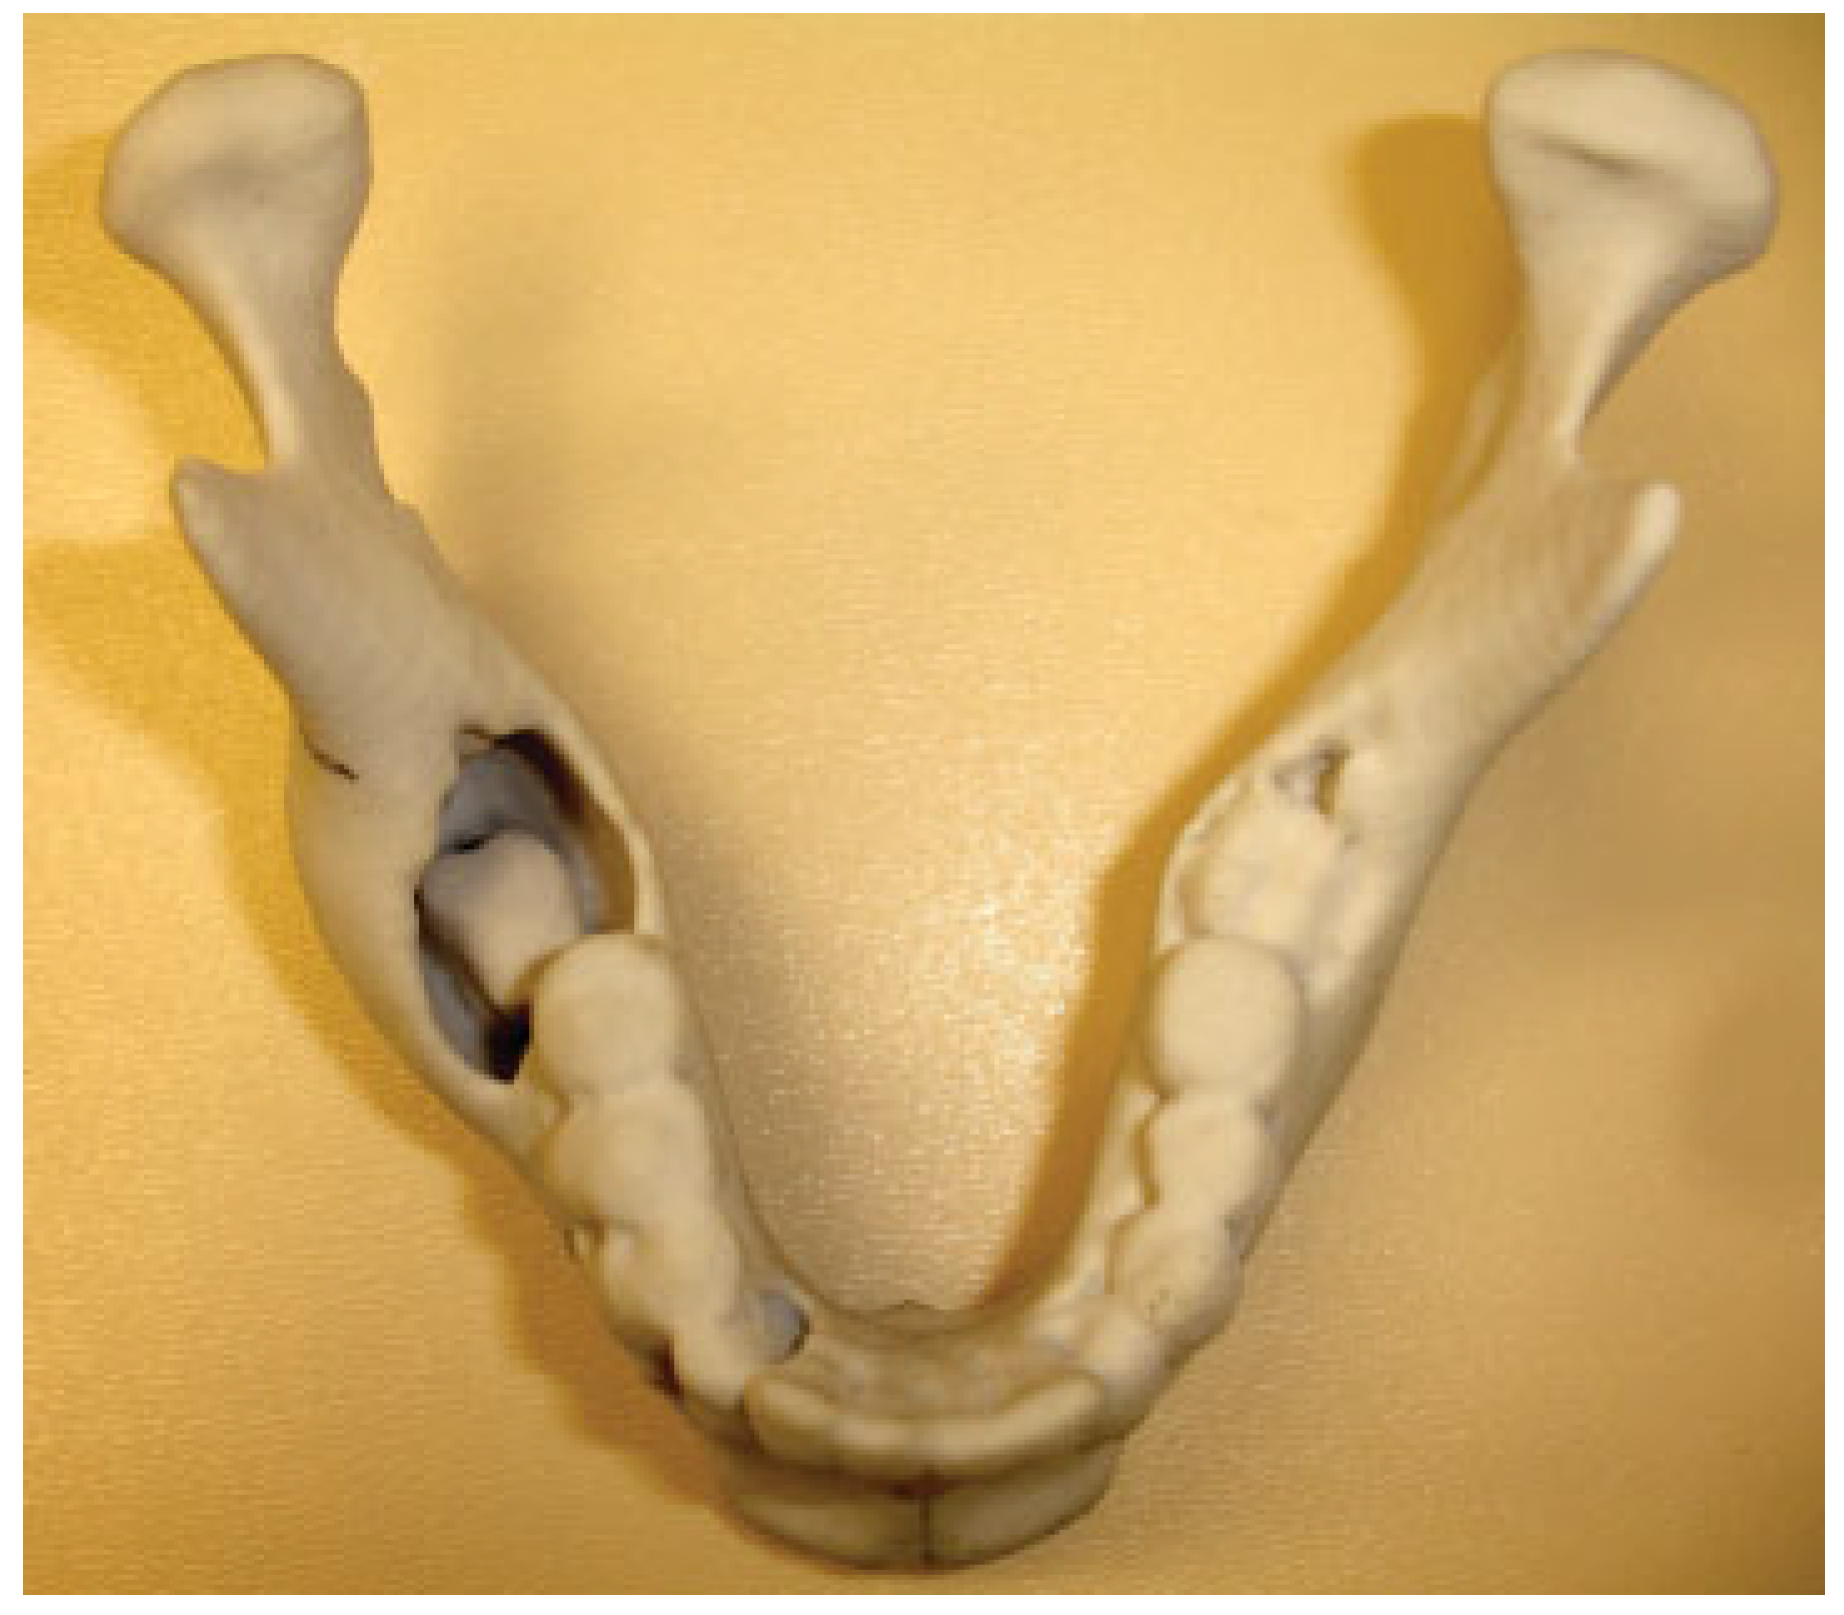

The fourth case was a 9-year-old white male referred to our service with a biopsy-proven ameloblastoma of the right mandible. Panoramic radiographic examination showed a unilocular radiolucent lesion extending from the right first mandibular molar up into the ascending ramus (Figure 4). A high-resolution CT scan was followed by the construction of a three-dimensional model (Figure 5). The resection with 1-cm margins was planned over the model extending vertically from the right sigmoid notch to the gonial angle and anteriorly through to the ipsilateral first premolar. Because of the marked lateral expansile nature of the lesion, the model and the specimen (prior to resection) were altered at the area of the inferior border to facilitate hardware adaptation (Figure 6). A prebent reconstruction plate was obtained and sterilized preoperatively. The resection was performed via a combined transoral and transcutaneous approach. Screw holes were drilled using the prebent plate as a template prior to completing the osteotomies. This was done to ensure correct position of the segments. After the resection, the plate was repositioned without modification utilizing the previous predrilled holes (Figure 7). The occlusion was assessed intraoperatively and was found to be unchanged from preoperatively. The total surgical time was 3 hours and 34 minutes.

One of the difficulties we encountered was the bending of the plate over a deformed model due to an expansile lesion. We solved this issue by modifying the model using the opposite site as reference (Figure 6). Coward et al. [8] described a technique to create a mirror image wax model for reconstruction of an ear using the contralateral unaffected side. Using the same principle, Hannen [9] reported two cases in which, with the help of software, the corresponding unaffected area from the contralateral side was digitally separated, mirrored, and fitted into the resection defect, obtaining a symmetric model used as a template for custom-bent plates. Another common complication is placement of the plate before performing the osteotomies. This was done on cases 4 and 5 with the objective of recording the position of the segments prior to resection. Modifying the mandible at expense of the tumor violates the oncological surgical principles and is not viable on the deformed morbid anatomy secondary to malignancy. An external pin fixation device could be placed to accomplish this goal when the screw holes cannot be drilled before the resection.

Figure 5. Anatomic three-dimensional model of the mandible. Noted lateral expansion and displaced second molar. Case 4.